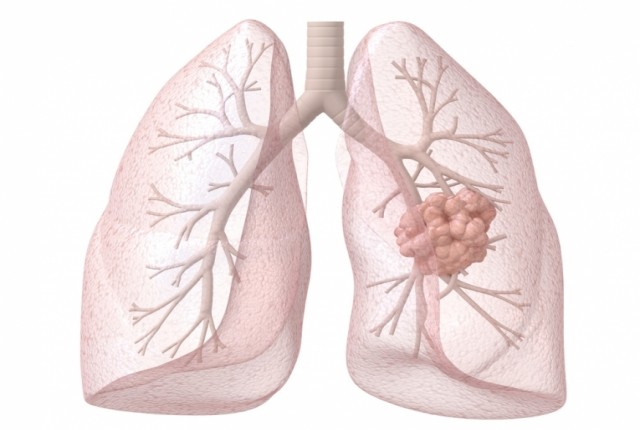

Καρκίνος του πνεύμονα-Τι τον προκαλεί και ποιοι κινδυνεύουν;

Τι προκαλεί καρκίνο του πνεύμονα;